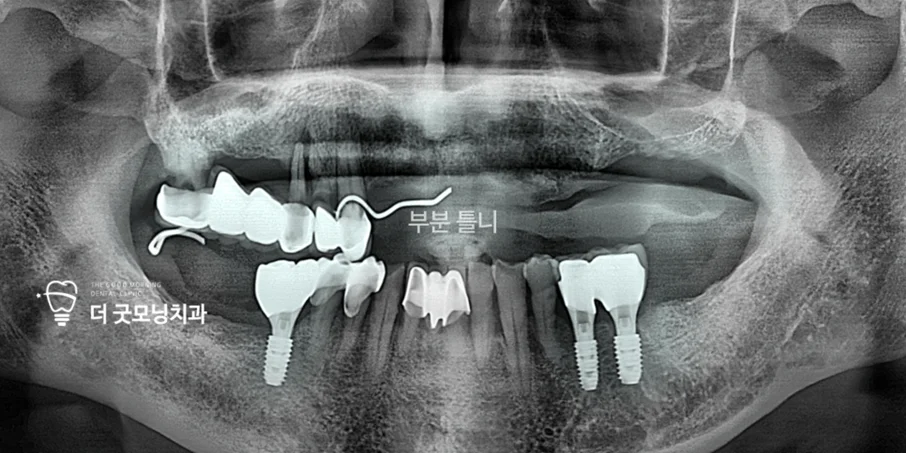

Step 3. 상악 치료 — 사보험 활용

하악 치료 완료 후, 상악은 기존에 사용하던 부분틀니를 활용하는 방법도 있었지만, 환자분이 전체 임플란트로 변경을 희망하셨습니다. 확인 결과 사보험에 연간 임플란트 3개 보장이 포함되어 있었습니다.

총 8개의 픽스처를 식립해야 하는 상황이었기 때문에, 양측을 한 번에 진행하면 보험 혜택이 제한됩니다. 이에 좌우를 나눠 치료 기간을 분산함으로써 보험 수혜 개수를 최대화했습니다.